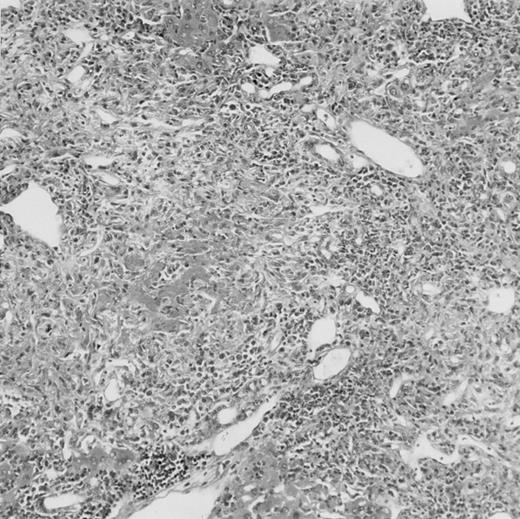

Histologic findings. Organs were collected at different times after BMT and tissue sections were stained with hematoxylin and eosin. Original magnifications for spleen (left) and liver (right) are ×40 and ×100, respectively. (A) B6 mice receiving FVB BM plus EpTK T cells. (B) Control group receiving BM only.

(C) B6 mice receiving FVB BM plus EpΔTK T cells and treated with GCV. (D) B6 mice receiving FVB BM plus EpΔTK T cells, treated with GCV, and developing a late onset GVHD (day 54).

FVB BM-grafted B6 mice: a model of lethal GVHD.We developed a model of GVHD resulting in 100% mortality soon after BMT using FVB mice, a strain not previously used as BM donors in experimental allogeneic BMT. We tested different combinations of recipient irradiation doses, as well as injected BM cell and CD3+ peripheral T-cell numbers. When 10-Gy–irradiated B6 mice were reconstituted with 107 FVB BM cells, we observed prolonged survival, whereas all ungrafted animals died before day 16 (Fig 2). In these conditions, more than 98% of splenocytes were of donor origin (Fig 3A). When 107 CD3+ peripheral T cells from mice of FVB genetic background were added to the FVB BMT, all animals died of GVHD between days 7 and 34 (Fig 2). Similar results were obtained using either PBS-treated mice receiving EpTK or EpΔTK peripheral T cells or GCV-treated mice receiving FVB nontransgenic peripheral T cells. Notably, this observation also indicates that both TK- and ΔTK-expressing T cells in the absence of GCV are fully competent to induce a lethal GVHD. Histopathologic examination of spleen and liver of these animals showed characteristic GVHD lesions such as (1) architecture disruption, necrosis, and congestion in the spleen; (2) hepatic periportal necrosis; (3) mononuclear portal infiltrates; and (4) endothelialitis of portal or centrolobular veinules (Fig 4A). By comparison, B6 mice receiving only FVB BM had a normal histology (Fig 4B).

Using this delivery mode, we observed that mice receiving a 7-day GCV treatment initiated at the time of transplantation were protected from GVHD. At day 60, the survival rate was 100% in the GCV-treated group receiving EpTK CD3+ T cells, and was still 92% at the end of a 120 day follow-up (Fig 2A). Protected mice were apparently healthy, presented no visible skin lesions, and gained weight comparably to controls receiving only BM (data not shown). Hematologic reconstitution was analyzed by flow cytometry at different times from day 14 to day 212. Splenocytes of GCV-treated animals were of donor H-2q origin in the B-cell (B220+) and non–B-cell (B220−) compartments, the latter containing donor Thy1.1+ T cells but no recipient Thy1.2+ T cells (Fig 3B). Finally, histological analysis in these animals showed nodular architecture in the spleen and no significant hepatocyte necrosis or portal mononuclear cell infiltrates in the liver (not shown) and similar to control animals receiving only BM. Taken together, these data indicate that a GCV treatment, administered at the onset of allogeneic BMT and with a course as short as 7 days, abrogates GVHD and allows a full recovery from the lethal irradiation.

Protection from GVHD was slightly less efficient in the group receiving EpΔTK CD3+ T cells. The survival rate was 79% at day 60 and 67% at day 120 (Fig 2B). However, two different outcomes must be distinguished. On the one hand, a majority of mice behaved as GCV-treated animals receiving EpTK T cells. They were apparently healthy, presented no skin lesions during a 120-day observation period, and showed complete donor-type hematologic reconstitution. There were no histological signs of GVHD in the spleen or liver (Fig 4C).